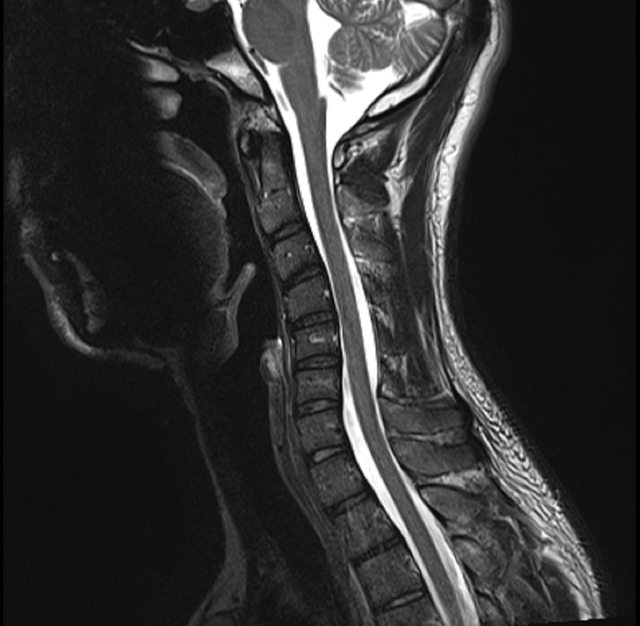

--- 目前做了檢查 - 頸椎 MRI 似乎不太正常 - Slight kyphosis of cervical spine (頸椎排列後凸) https://i.imgur.com/BUnDwSd.png

https://i.imgur.com/tC0JNs6.png